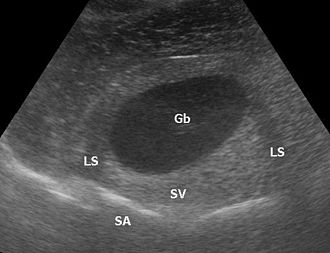

Die Sonografie ist das wichtigste Verfahren bei der Differentialdiagnose eines akuten Abdomens, bei Gallensteinen oder bei der Beurteilung von Gefäßen und deren Durchlässigkeit, vor allem an den Beinen. Weiterhin wird sie standardmäßig zur Untersuchung der Schilddrüse, des Herzens – dann Echokardiografie oder Ultraschallkardiografie (UKG) genannt –, der Nieren, der Harnwege und der Harnblase benutzt. Durch den Einsatz von Echokontrastverstärkern (Kontrastmittel) ist in geeigneten Fällen eine weitere Verbesserung der Diagnostik möglich.

- Gallenblase – Gallengang